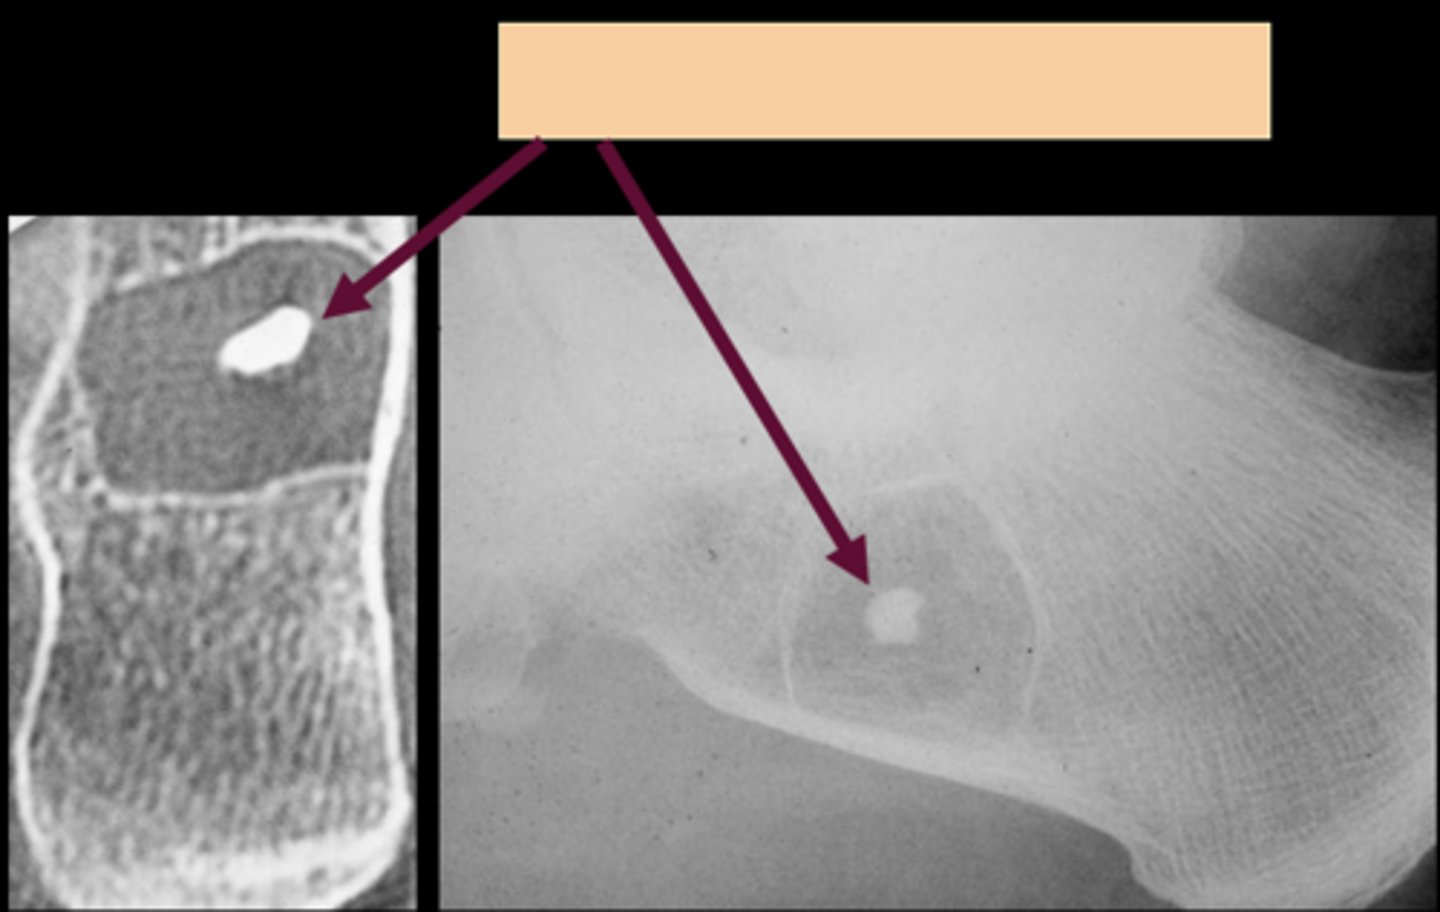

Target sequestrum

ID sign of intraosseous lipoma

<p>ID sign of intraosseous lipoma</p>

Intraosseous lipoma

- M=F

- 5-70 y.o.

- Asymptomatic

- Central target sequestrum

- Calcaneus

- Tibial metaphysis

- Fibular metaphysis

<p>- M=F</p><p>- 5-70 y.o.</p><p>- Asymptomatic</p><p>- Central target sequestrum</p><p>- Calcaneus</p><p>- Tibial metaphysis</p><p>- Fibular metaphysis</p>